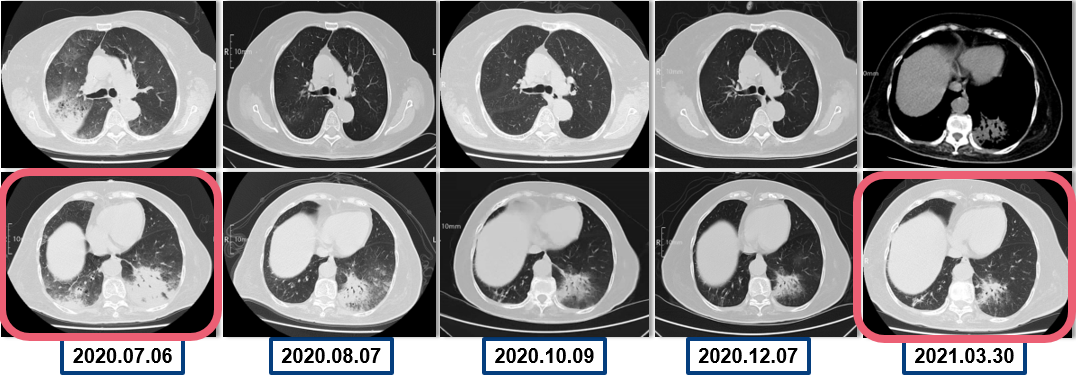

为提升肺癌前线免疫联合抗血管治疗的诊疗观念,学习与追踪肺癌领域诊疗最前沿知识,充分交流免疫/抗血管用药不良反应管理临床经验,【An例说】肺癌病例项目,征集大量临床高质量免疫联合抗血管治疗肺癌病例,并邀请全国各区域中青年及高职称医生与顶级TOP KOL互动发声!通过理念结合实践,研究结合病例,线上联动,共同促进学术由KOL/ROL向中青年医生下沉,为提升我国肺癌诊疗整体水平势在必行。免疫治疗的出现,对于晚期肺癌患者而言,显著提高了患者的生存质量及延长生存期,多项研究表明免疫治疗对于PD-L1表达阴性的患者也具有一定的治疗效果。为此,上海长海医院(海军军医大学第一附属医院)团队为您带来一例肺癌免疫联合抗血管病例分享。 患者,女性,78岁 2017年体检时发现左下肺结节,未行诊断及治疗。 2018.11.21、2019.09.24胸部CT均提示病灶较前变大,仍未诊治。 影像学检查 2020.01初逐渐出现胸闷、气短,活动后尤为明显。多次就诊于当地医院输液治疗(具体不详)。入院前2周胸闷,气急症状加重,无发热,无明显咳嗽,咳痰。2020.06.23入院。 影像学检查 既往史:高血压病30余年,最高血压170/90mmHg,规律服用美托洛尔12.5mg+利血平 0.1mg/日,自诉血压控制可。 个人史:无特殊 婚育史:无特殊 家族史:无特殊 T:37.0℃ P:104次/分 R:30次/分 BP:134/58mmHg 右肺及左肺可闻及湿罗音,左下肺呼吸音弱,无胸膜摩擦音。 心脏查体无异常。 入院后 CT引导下肺穿刺 穿刺后无咳嗽咯血,胸闷气急症状无加重。 6.25 出院等病理。 自行口服易瑞沙治疗,家中持续吸氧。 出院后3天突发病情变化: 6.28 凌晨1点左右,如厕后出现呼吸困难加重,晕倒。家属约2点发现,送至急诊,急诊予化痰、平喘、抗感染等对症治疗。 影像学检查 急诊检验检查: 【血气分析】PH 7.35、PO2 45.9mmHg、PCO2 62.6mmHg 【BNP】23.38pg/ml;【D-二聚体】0.32 【血常规】WBC:9.23×109/L、RBC:3.58×1012/L、HGB:98g/L、N%:80.2%、PLT:203×109/L。 【炎症指标】CRP:2.95mg/L;ESR:4mm/H;PCT:0.045ng/ml 【心电图】1. 窦性心动过速、2. ST-T异常。 血气分析 2020.06.29再次入院:左下肺腺癌、Ⅱ型呼吸衰竭、右肺阴影待查。 右肺渗出原因分析:感染?肿瘤进展?药物相关? 血常规变化: 选择治疗方案: 1. 两肺炎症,纵隔稍大淋巴结,炎症较2020.6.24进展,建议抗炎治疗后复查; 2. 左侧胸腔少许积液; 3. 两肺肺气肿、肺大泡,右肺中叶钙化灶; 4. 右侧第4肋骨皮质扭曲,请结合临床; 5. 甲状腺两侧结节,请结合超声。 右下肺腺癌 PD-L1无表达 抗血管生成与免疫联合的优点: 1、抗血管生成,靶点全面、强效抑制 2、抑制肿瘤细胞增殖和迁移,重塑肿瘤微环境,联合增效 3、肿瘤血管正常化及重塑,减轻免疫抑制状态 4、增加免疫效应细胞浸润 5、免疫刺激作用,激活免疫效应细胞 信迪利单抗联合安罗替尼的临床研究:这是一项前瞻性、非随机、三臂、Ib期临床研究。 临床研究试验设计 临床研究PFS和OS曲线 安罗替尼联合信迪利单抗一线治疗NSCLC,ORR达72.7%,DCR达100%,mPFS=15.6m,24m,OS率83.9%,表现出良好的治疗潜力。 派安普利单抗联合安罗替尼的临床研究:随机、双盲、多中心III期临床研究(NCT03866980) 临床研究试验设计 安尼可联合安罗疗效的ORR和DCR分析 数据截止日期:2021.1.13,共26例患者入组安尼可联合安罗替尼组,21例患者至少完成一次疗效评价。 帕博利珠单抗+安罗替尼 8mg。 治疗过程影像学检查 疗效评估: 2021.08.03: 疗效评估PR,截止目前PFS=15m。 该病例采用PD-L1抑制剂帕博利珠单抗联合小分子多靶点抗血管生成药物安罗替尼治疗老年肺腺癌患者,获得了15个月的PFS,提示对于驱动基因阴性,PD-L1无表达的晚期非小细胞肺癌患者免疫联合抗血管生成药物治疗是NSCLC患者一线治疗的选择和手段之一。 Impower150研究显示,贝伐珠单抗联合PD-L1抑制剂阿替利珠单抗+化疗显著改善了无突变非鳞NSCLC患者的PFS,中位OS达19.4个月(对照组14.7个月),ORR为71%。但治疗相关的毒副反应较大,一定程度上影响患者生活质量。小分子TKI联合免疫作为肿瘤去化疗联合治疗模式,越来越受到关注,前期探索性前瞻性随机临床研究包括信迪利单抗+安罗替尼(ACTION研究)、派安普利单抗+安罗替尼(AK105-301研究)和卡瑞利珠单抗+Apatinib/ target=_blank class=infotextkey>阿帕替尼(SHR-1210-III-315 研究)等一线治疗驱动基因阴性晚期NSCLC均得到了较好结果, 信迪利单抗联合安罗替尼组ORR达72%,DCR100%,中位PFS15.6个月,2年OS率83.9%,耐受性良好,显示出多靶点抗血管生成药物联合的良好应用前景。 免疫与抗血管生成药物以及与其他药物或方式联合该如何排兵布阵,肺癌治疗如何真正践行个体化和精准化,还有许多问题和挑战,有待进一步研究拓展和证实。 病例分享 焦洋 教授 上海长海医院,副主任医师,副教授 海军军医大学长海医院呼吸与危重症医学科 美国田纳西州大学附属医院呼吸与危重症医学科访问学者 上海市医学会呼吸分会感染学组秘书 中国老年医学会感染诊治与合理用药学术委员会委员 专业方向:疑难、复杂肺部感染及呼吸危重症的救治,肺癌的早期诊断和治疗。 专家点评 韩一平 教授 海军军医大学第一附属医院 呼吸与危重症医学科教授、主任医师 博士生导师 海军军医大学第一附属医院临床教育中心主任 中华医学会呼吸分会肺癌学组委员 中国医药教育协会肺部肿瘤专委会常委 中国医师协会全科分会委员,上海全科分会副会长 《中国肿瘤生物治疗杂志》《中国全科医学杂志》 《第二军医大学学报》《内科年鉴》等编委 获校“特级优秀教师”,上海市“育才奖” 首届上海“最美女医生” 主编发表教材或专著5部,近年发表文论50余篇 *仅供医学药学专业人士阅读 文章来源:ONCO前沿案例详情